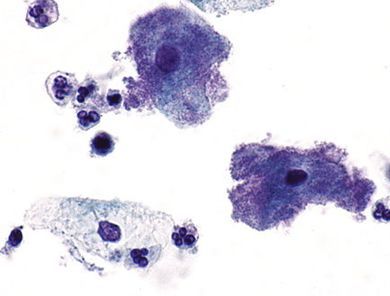

Посев уреаплазмы — «золотой стандарт» диагностики парвум уреаплазмы и других ее типов. На питательные среды высевают выделения из мочевыводящих путей.

- Бактериологическое исследование позволяет определить концентрацию микроорганизмов, но не делает различий между типами Ureaplasma urealyticum и Ureaplasma parvum. В случае положительного результата будет указано следующее: «Рост Ureaplasma urealyticum будет получен при концентрации 10 x КОЕ / мл», что может означать как U.urealyticum, так и U parvum.

- Молекулярно-генетическое исследование определяет уреаплазму с видовой точностью. В то же время более современное количественное исследование в реальном времени (так называемая ПЦР в реальном времени) определяет концентрацию микроорганизмов в формате «геномный эквивалент на миллилитр», что на один логарифм больше, чем традиционные КОЕ / мл [15] .